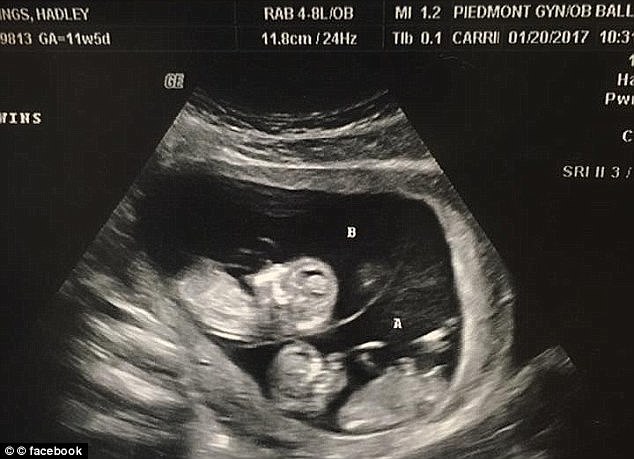

▼兩年之後,哈德莉再度懷孕而且還是雙胞胎,他們相信是上帝補償給他們的孩子,於是將會用死去的兩個兒子名字來為他們命名。